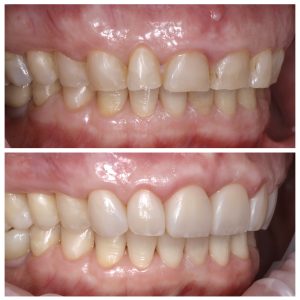

Visų nudilusių dantų plombavimas

Būklė, kai reikalingas visų nudilusių dantų plombavimas, susiformavo dėl dviejų priežasčių: amžiniai pokyčiai ir bruksizmas (dantų griežimas). Priekinių dantų atkūrimui buvo pritaikytas priekinių dantų estetinis plombavimas, plombuojant visą danties paviršių.

Galutinis rezultatas – natūrali ir autentiška šypsena. Tačiau svarbi ne tik atkurta dantų estetika. Mūsų odontologai pabrėžia, jog po gydymo, kai atliekamas visų dantų plombavimas ir atkūrimas, stipriai pagerėja sąkandžio būklė. Atkurta pilnavertė dantų anatomija apsaugo žandikaulio sąnarius nuo pertempimo ar priešlaikinio susidėvėjimo.

Visų dantų plombavimas prieš ir po Nudilusių dantų estetinis plombavimas prieš ir poVisų nudilusių dantų plombavimas prieš ir poViršutinis dantų lankas prieš ir po plombavimoApatinis dantų lankas prieš ir po plombavimo